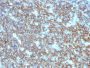

Positive Control

Daudi, Raji, and U266, and human lymphocytes. Lymph nodes and tonsils.

B-cells|Lymphocytes

Leukemia/lymphoma

Recognizes a protein of 30-33 kDa, which is identified as CD20. It is a non-Ig differentiation antigen of B-cells and its expression is restricted to normal and neoplastic B-cells, being absent from all other leukocytes and tissues. CD20 is expressed by pre B-cells and persists during all stages of B-cell maturation but is lost upon terminal differentiation into plasma cells. This antibody can be used for immunophenotyping of leukemia and malignant cells, B lymphocyte detection in peripheral blood and B cell localization in tissues. It reacts with the majority of B-cells present in peripheral blood and lymphoid tissues and their derived lymphomas. In lymphoid tissue, germinal center blasts and B-immunoblasts are particularly reactive. It is a reliable antibody for ascribing a B-cell phenotype in known lymphoid tissues. Rarely, CD20-positive T-cell lymphomas have been reported. Reactivity has also been noted with Reed-Sternberg cells in cases of Hodgkin's disease, particularly of lymphocyte predominant type. Primary antibodies are available purified, or with a selection of fluorescent CF® Dyes and other labels. CF® Dyes offer exceptional brightness and photostability. Note: Conjugates of blue fluorescent dyes like CF®405S and CF®405M are not recommended for detecting low abundance targets, because blue dyes have lower fluorescence and can give higher non-specific background than other dye colors.